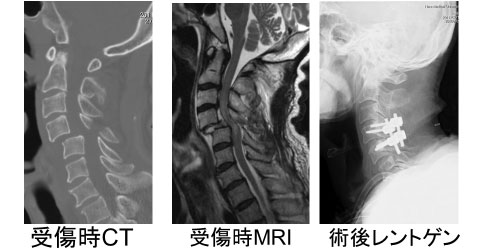

図4:第4頸椎脱臼骨折

MRIで脊髄の損傷がわかる。手術で脱臼を整復し螺子にて後方固定を施行している